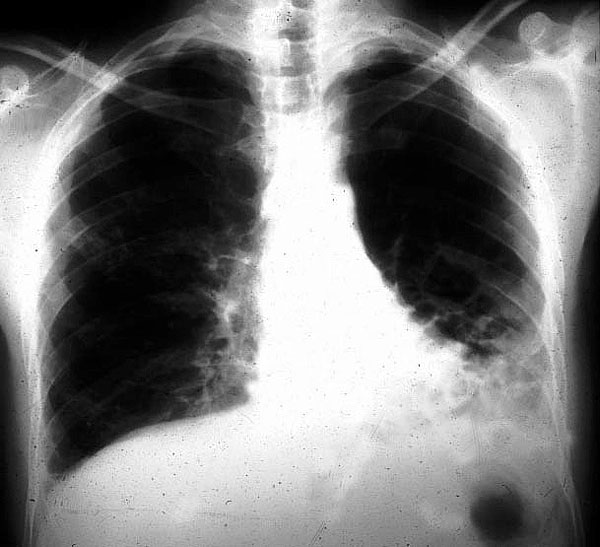

Placa 34